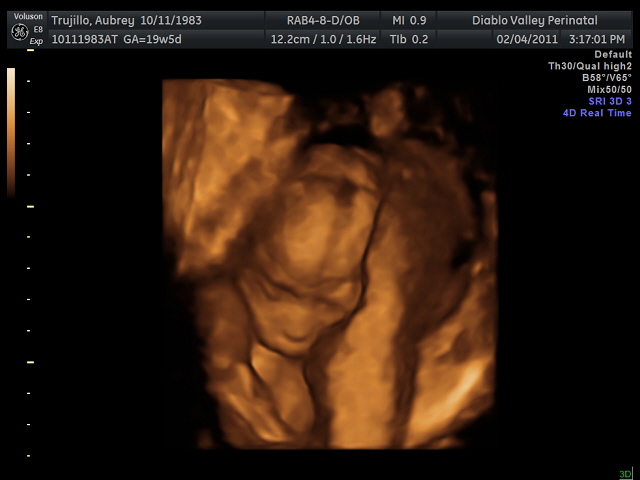

Baby looks like Matthew, I think... but it could just be the bald head that's making me think that!  It was moving around a lot and I swear it waved at us :)12 weeks

20 weeks - profile20 weeks - Profile again20 weeks - Right foot!20 weeks - sucking thumb!!!!20 weeks - hand near face20 weeks - flexing his bony arms!20 weeks - hiding from mommy and daddy!20 weeks - it's a boy!33 weeks - 3D!33 weeks - 3D!33 weeks - 3D!